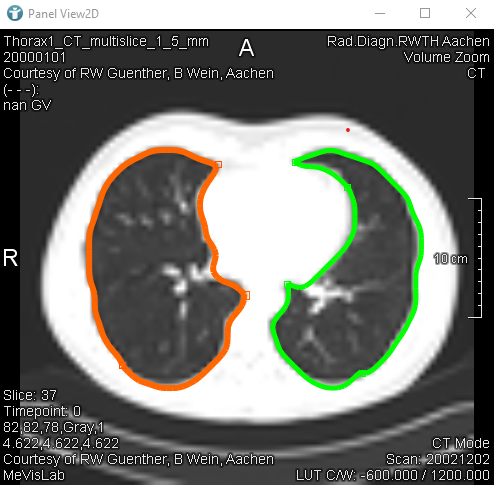

CSOs can also be grouped together. The following image shows two different CSOGroups. Groups can be used to organize CSOs, in this case to distinguish the CSOs of the right and the left lung. Here you can find more information about CSOGroups.